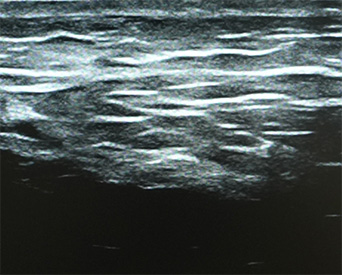

기존 울쎄라 초음파는 8mm 깊이까지만 확인 가능해

지방층이나 뼈 깊이 등 피부 내부 전체 구조를 보기 어렵습니다.

이를 보완하기 위해 더퍼스트피부과는 4cm 깊이까지 확인 가능한

최신형 진단 초음파 장비를 도입하여 피부 진피-지방-근육-뼈 깊이까지

정밀하게 파악하여 에너지와 샷수를 조절하는 시술 플랜을 세웁니다.

울쎄라 초음파

DEEP SONO™ 초음파